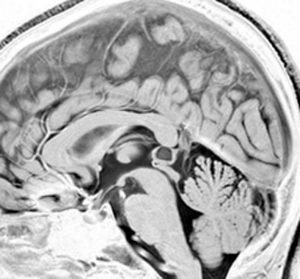

若い女性にできた,症状の全くない松果体のう胞です。右側は拡大図で,8 mmくらいの大きさでしょうか。もちろん何もする必要はありません。たくさん発見されるものです。